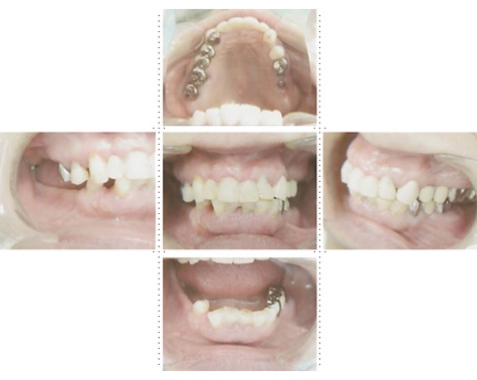

症例1

58才 女性

嘔吐反応が激しく入れ歯を入れると気持ち悪くなってしまうと、インプラント希望で来院されました。

上顎左右奥に4本ずつ計8本のインプラント埋入。下顎左右奥に3本ずつ計6本のインプラント埋入上下顎とも全体的にセラミックを使用した冠をセット。